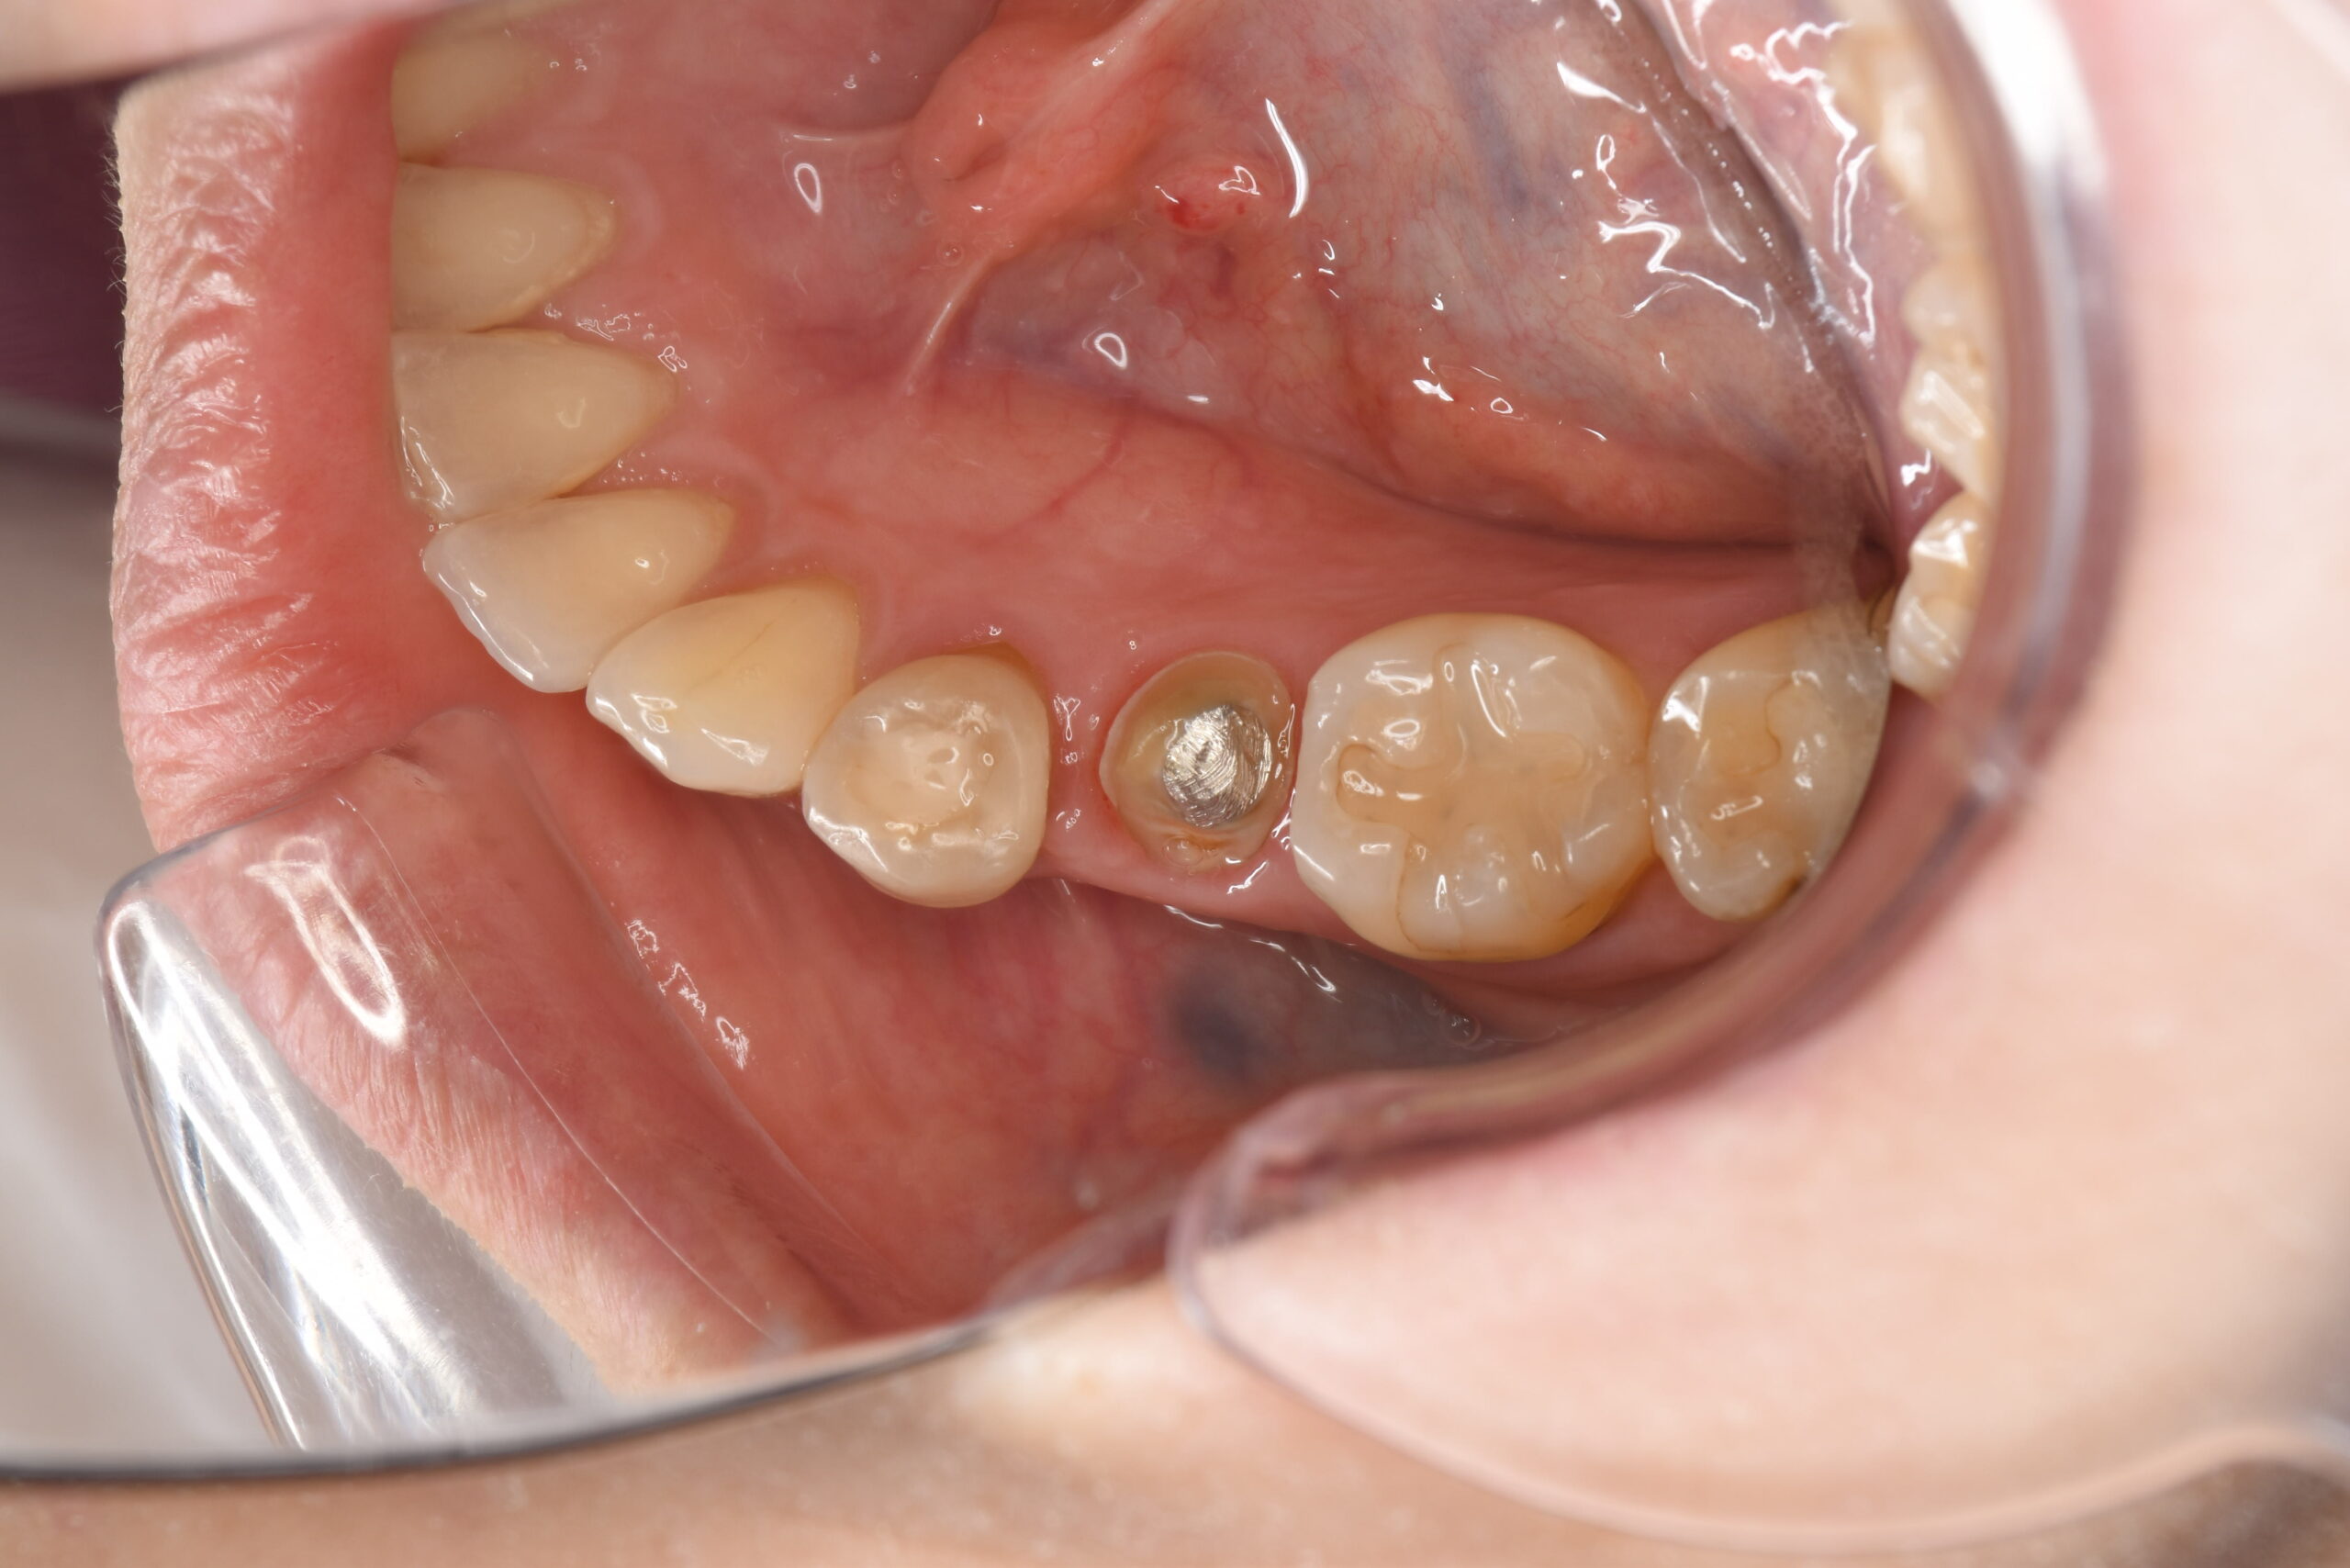

他院に通われていた方ですが、虫歯の再発が多いため今後は再発のリスクとアレルギーの心配が少ない治療法を受けたいとのことで来院されました。

| 銀歯が被っている部分をジルコニアにて被せ物処置を行なった |